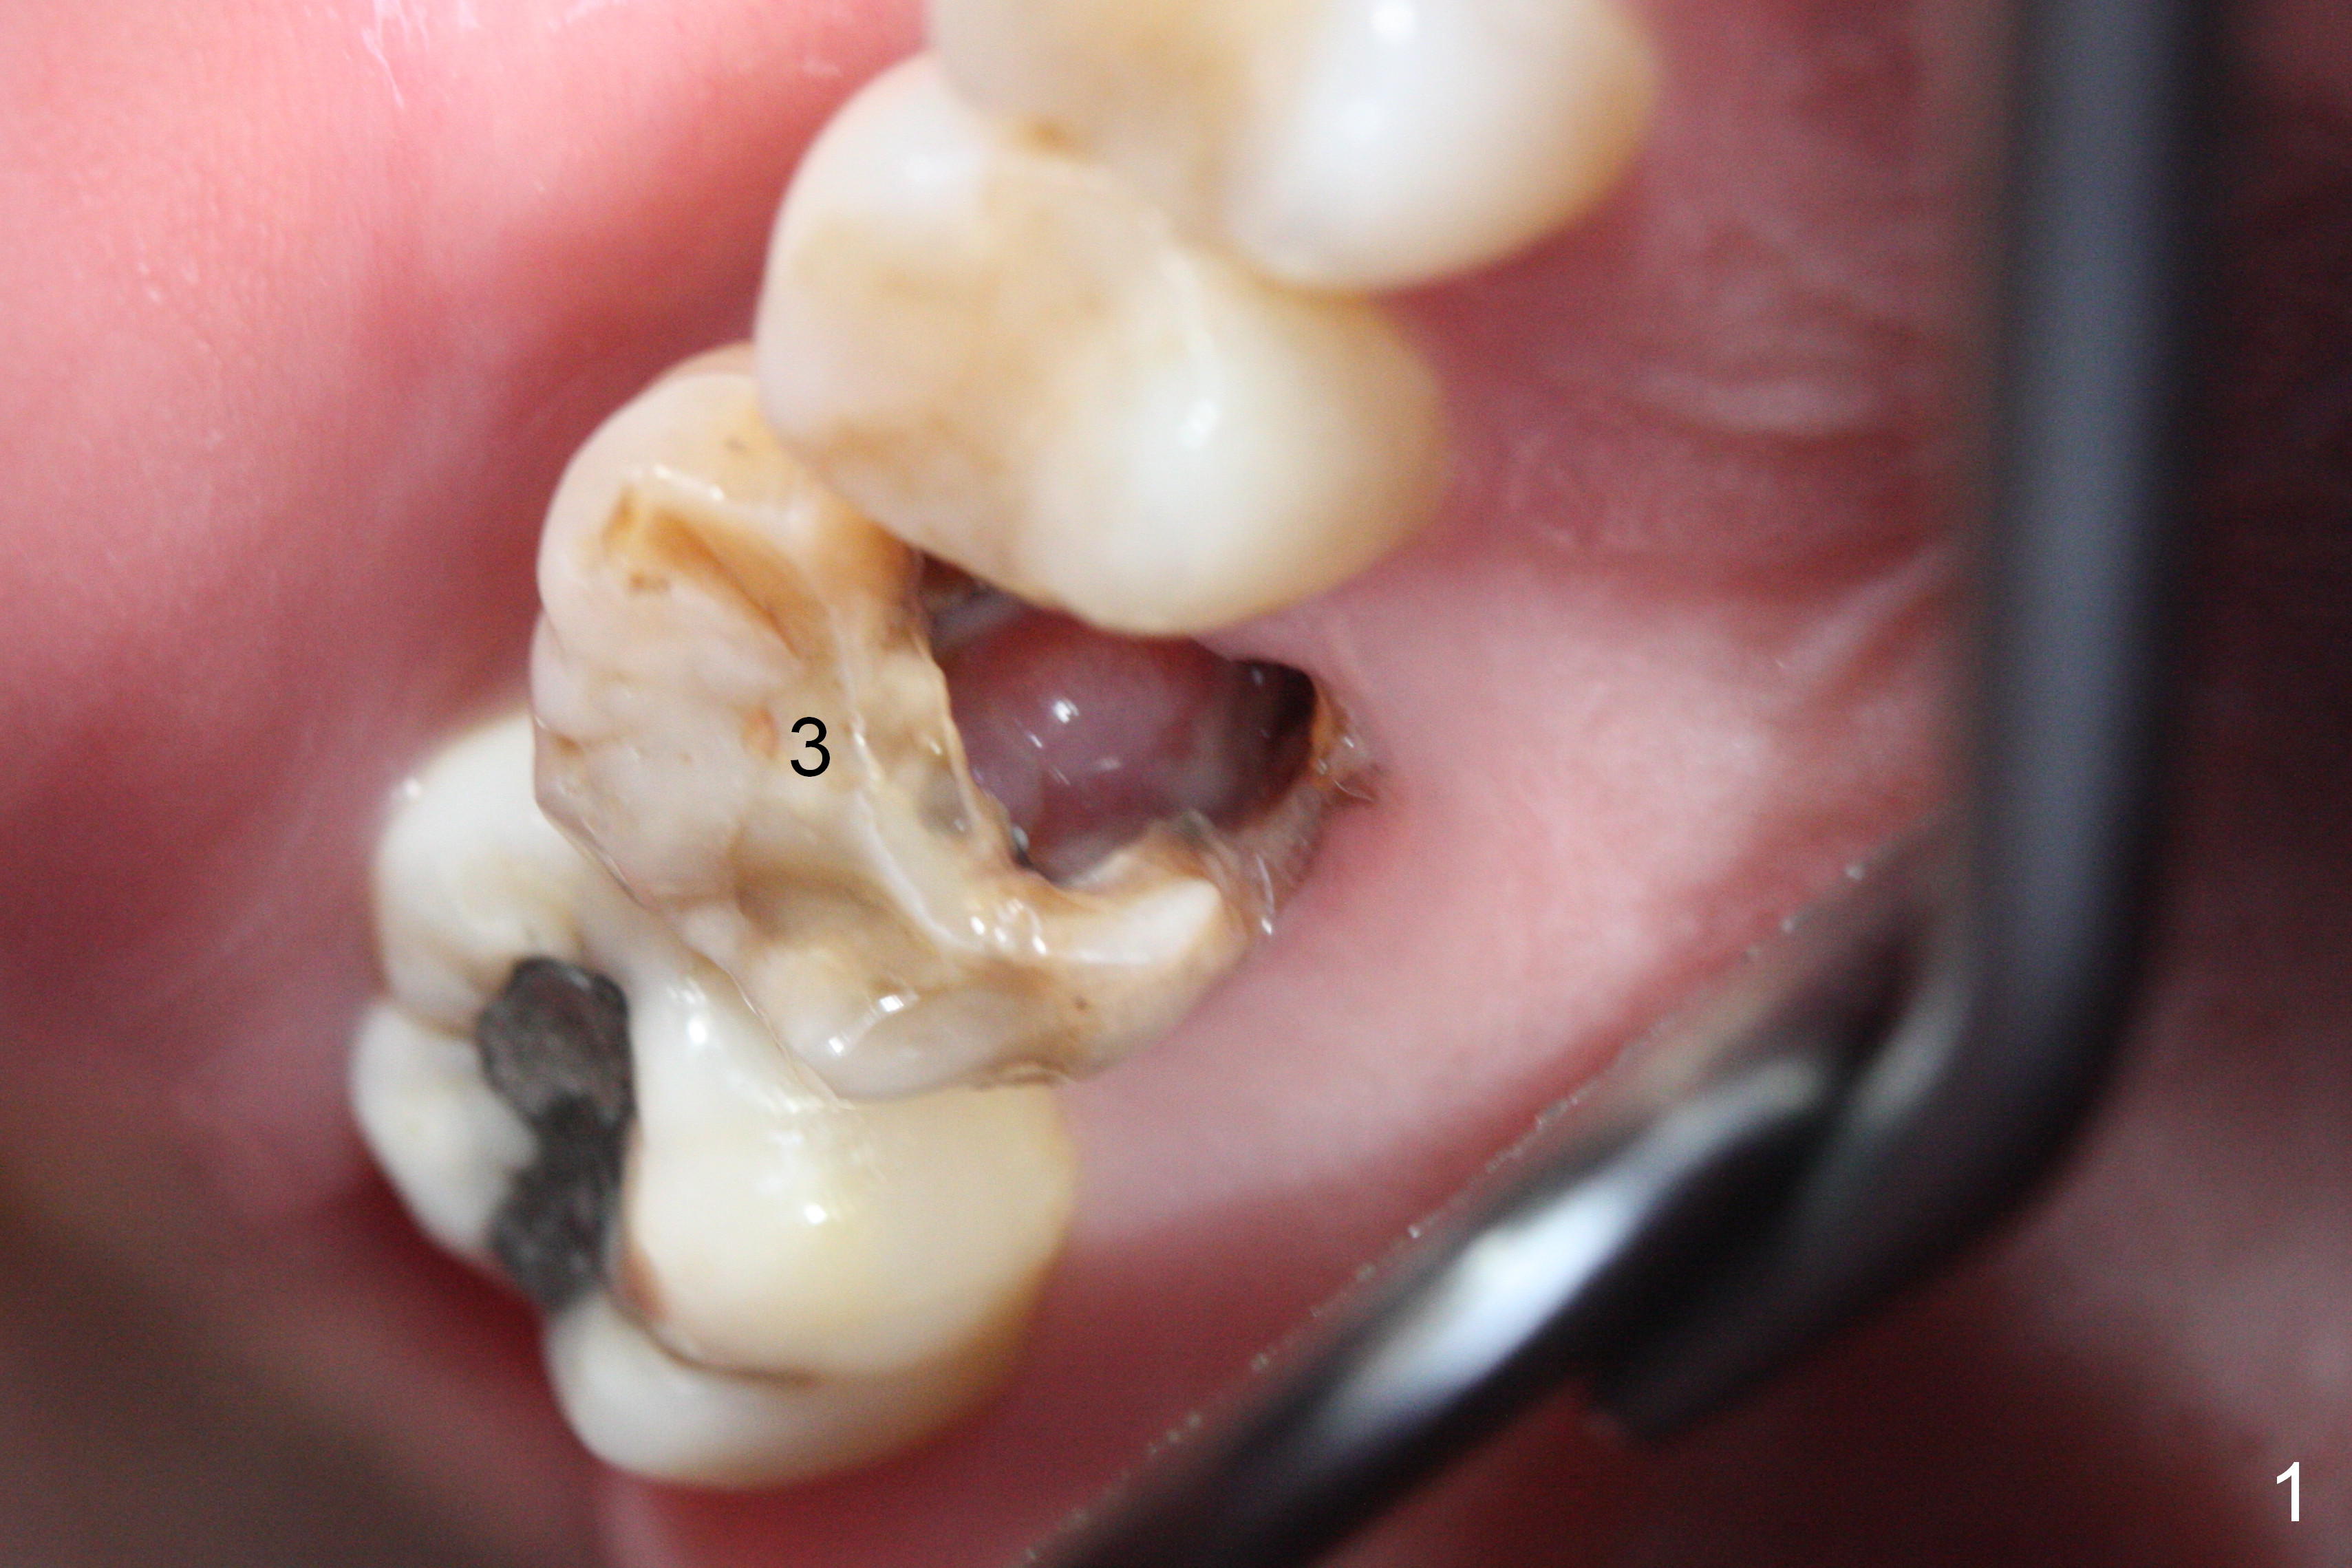

The polyp in the pulpal chamber of the tooth #3 (Fig.1) originates from the distal gingiva. After extraction, buccal plate perforation is found apical to the distobuccal socket. The septum is large (Fig.2 S). Osteotomy is initiated in the middle of the septum with 1.6 mm drill until 3.8 mm Magic Drill (MD) (Fig.3). The last drill is 4.3 mm, followed by 4.8 mm Magic Expander since the palatal wall of the osteotomy is thin after the last drill. A 5x13 mm IBS implant is placed with ~ 45 Ncm. The apical portion of the 3 sockets is filled with Osteogen plug and the coronal portion with autogenous bone (harvested from MD), mixed with allograft and Osteogen (Fig.4 * as well as collagen plug in the most superficial portion of the sockets). A 6.5x4(4) mm pair abutment (Fig.4 A) is placed to hold an immediate provisional in place.